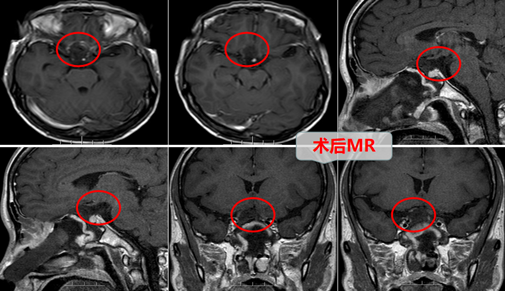

为了不耽误邱大姐的治疗,邱大姐的家属在市医院查明病情后连忙买了车票陪邱大姐一起来到广东三九脑科医院进行求医治疗。广东三九脑科医院门诊拟“鞍结节脑膜瘤”收住神经外十科。外十科团队在欧阳辉主任的带领下,非常重视,仔细地分析了病情,由于邱大姐的眼睛接近“失明”,要尽力、尽快手术挽救视力。随即外十科对邱大姐的手术进行了详细的讨论和安排:MR示“鞍结节偏右侧团块状占位性病变,呈等T1长T2异常信号影FLAIR序列呈高信号,范围约20×13×20mm,病灶轻度突入鞍内,肿瘤压迫视神经、视交叉,与邻近右侧颈内动脉关系密切”。外十科团队在结合上述信息的基础上,在征得邱大姐及其的家属的同意后,迅速为邱大姐实施了“神经内镜下扩大经鼻蝶入路,鞍结节脑膜瘤切除术+颅底重建术”。术中精准地切除肿瘤,仔细、妥善地保护视神经,并为视神经、视交叉减压,全程为微创手术,整个手术过程顺利,神经内镜显示全景视野和多角视野,为主刀医生提供多角度观察,最大限度减轻了对鼻腔内正常结构的损伤,真正做到了微创,并要使患者快速康复。

在手术完后的几天后,邱大姐的儿子来看望自己的母亲,并随手将病房的大灯打开了;邱大姐突然说“大白天的,开啥大灯呀。”,邱大姐的儿子连忙靠近病床询问母亲“妈,你看得到啦?”。邱大姐回答“是的,这不是我儿子吗?妈都看到你的大脑门了”。这时候邱大姐的儿子才确定母亲的视力恢复了,连忙将这个好消息告诉了父亲并向外十科团队进行道谢!此外他还惊奇的提出了自己的疑问“做完手术才这几天,母亲的视力怎么这么快就恢复了呢”。